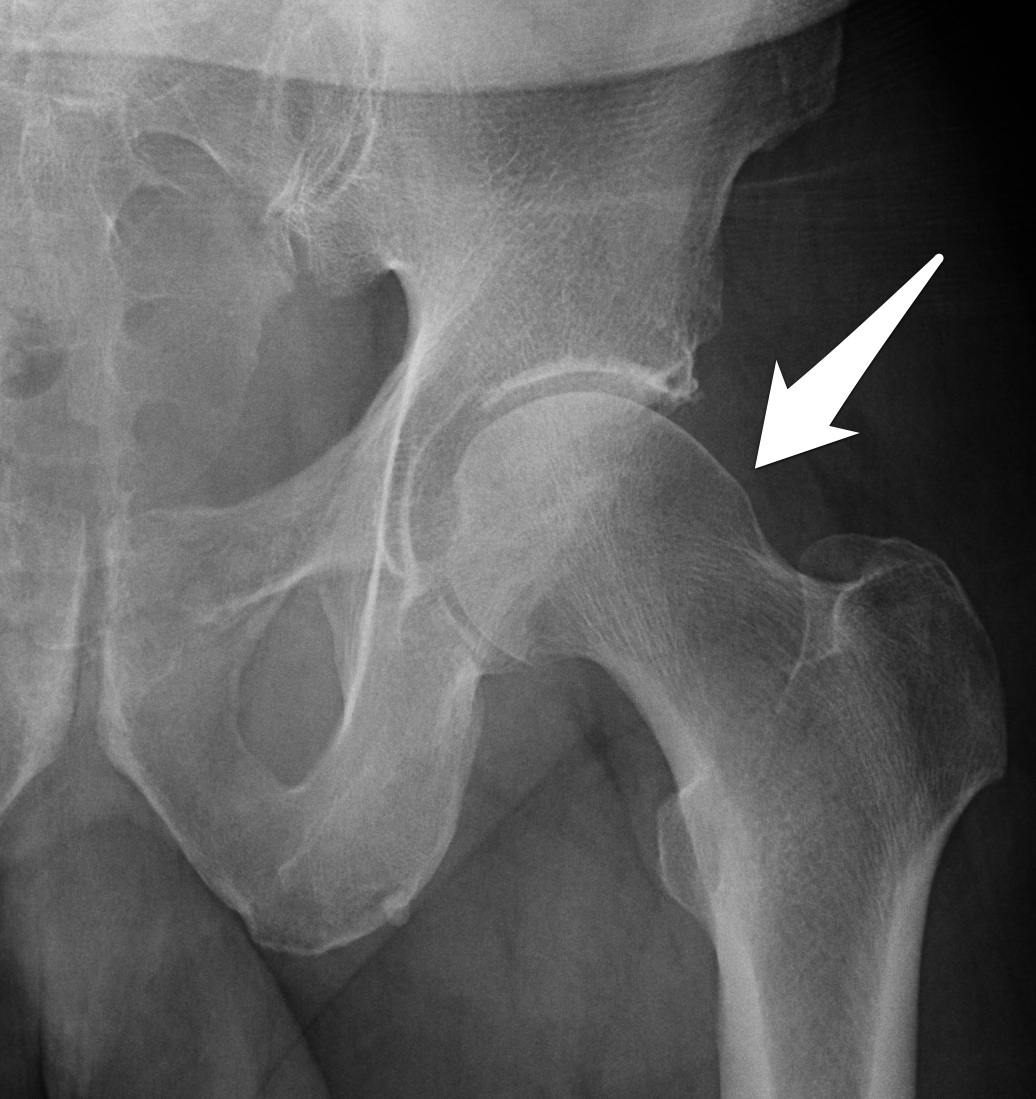

Cam Type Fai X Ray . Arrows show herniation pit caused by cam type of femoroacetabular impingement. Iil = ilioischial line, aw = anterior wall, pw = posterior wall, f = fossa. Your doctor may order imaging tests to help determine whether you have fai. Femoroacetabular impingement (fai) is the abnormal contact between the femur and acetabulum which may lead to labral damage, various degrees of chondral injury and progressive. Preoperative images of a 33 years old male with cam type fai are illustrated. Learn about the risk factors, clinical presentation, radiographic. (a) the ap pelvic radiograph reveals an asphericity at the.